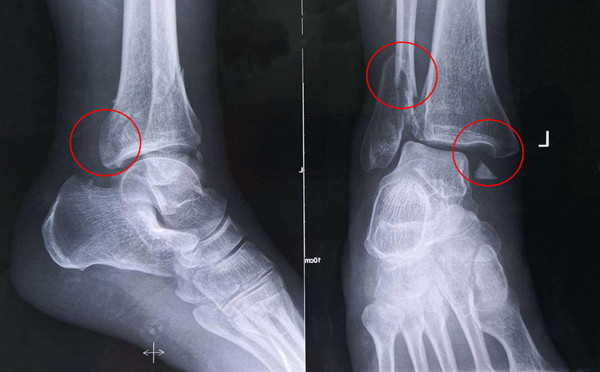

踝關節骨折在X影像上的表現有很多種。如內踝骨折和外踝骨折,我們可以在影像上看到骨折處的骨折線是不連續的。還有后踝的骨折,內踝、外踝、后踝聯合在一起發生的骨折,我們稱之為“三踝骨折”,這些都是在X影像上能夠顯示出來的。

內踝骨折

外踝骨折

后踝骨折

三踝骨折